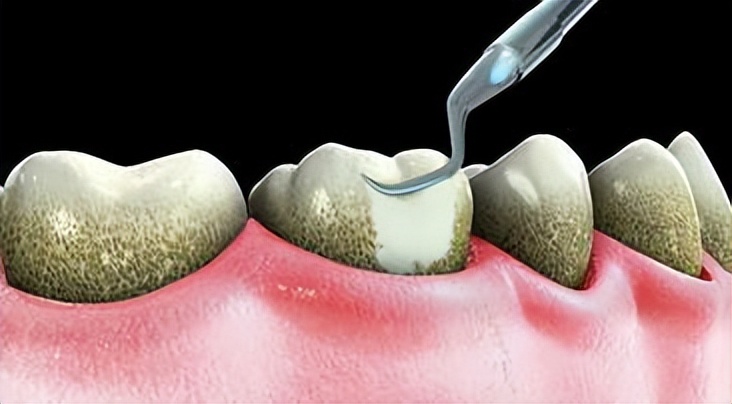

定期洗牙

每隔半年到一年请牙医洗牙,尤其是钙化后的牙结石或囊袋深部的食物残渣、牙齿斑或者牙结石,只有靠牙医才能清除干净。